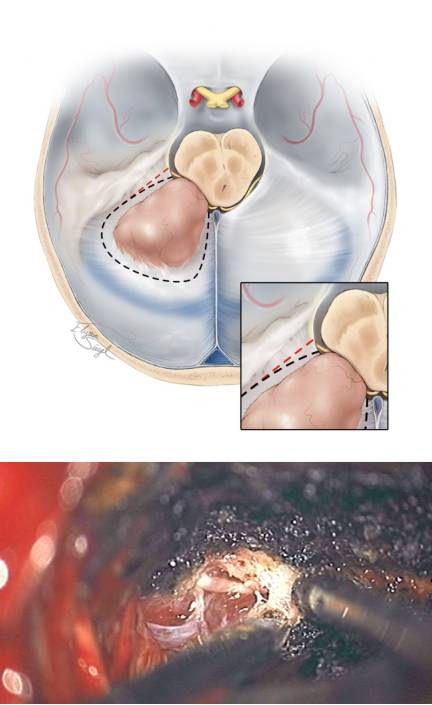

图9. 在切除天幕游离缘的时候要注意保护滑车神经(上方插图)。若要沿着红色虚线切除将会损伤神经,而沿着黑色虚线则利于神经保护。另外,颞叶后方基底部的脑实质肿瘤需要T形切口切开天幕。切除左侧岩骨天幕区域脑膜瘤的术中图片证实了滑车神经在肿瘤和天幕前缘进入硬模(下图)。

图10. 在充分保护滑车神经的情况下,天幕切口可从岩骨边缘延伸直到中线以包含肿瘤基底区域。在少数情况下,如术中发现汇入天幕的枕叶引流静脉阻挡视野,可将其牺牲。沿中线切开天幕时必须注意保护直窦以及其分支。天幕有可能存在静脉湖,而天幕的静脉出血可以通过浸泡凝血脢的明胶海绵压迫止血,而双极电凝则会皱缩天幕,扩大裂口而加重出血。

像上图所示的方式靠近肿瘤并切开天幕将会有助于减少肿瘤血供,并提供一个相对无血的区域来切除和分离肿瘤。

图11. 在切开天幕暴露肿瘤后,可通过吸引器和双极电凝来对质软肿瘤行内减压,而对纤维性质地坚硬的肿瘤则可通过吸引器和CUSA(超声吸引器)配合来进行切除。但在内减压肿瘤过程中不应在视线不及的瘤壁外侧操作。